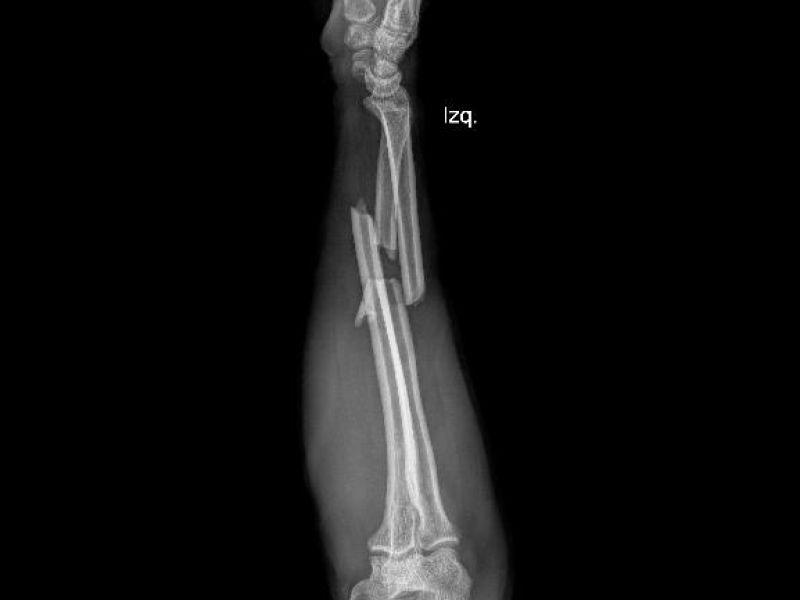

OSTEOSÍNTESIS

Paciente en postoperatorio de osteosíntesis de radio distal, que al inicio de la terapia presentaba marcada rigidez articular y limitación funcional. El proceso de rehabilitación convencional ha sido limitado, con solo dos sesiones de fisioterapia realizadas por EPS.

Las imágenes corresponden a la evolución a los dos meses de seguimiento, donde se documenta el estado funcional actual y los cambios observados pese a la baja frecuencia de terapia convencional.